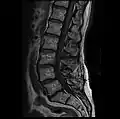

MRI lumbar spine with degeneration, post-hemilaminectomy L4-5 (sagittal T2 FRFSE) -

MRI lumbar spine with degeneration, post-hemilaminectomy L4-5 (sagittal T1 FSE) -

MRI lumbar spine with degeneration, post-hemilaminectomy L4-5 (sagittal FAST STIR) -